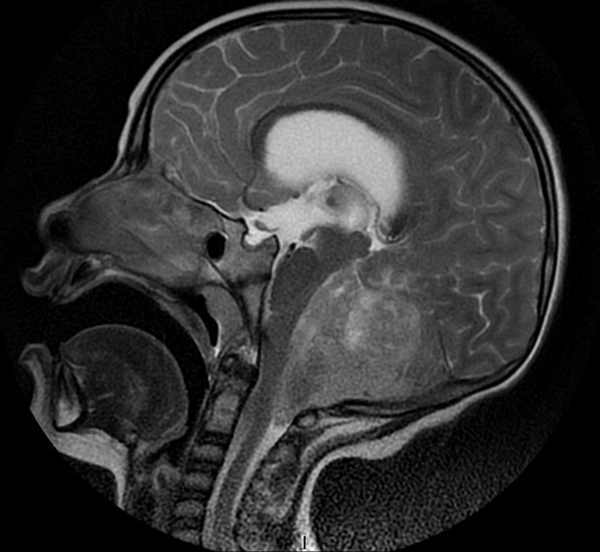

En resonancia magnética (RM) de cerebro se observa tumoración heterogénea sólida o sólido-quística con áreas de hemorragia, quistes y calcificaciones, que capta contraste en forma variable. (Fig. 1, 2, 3, 4). El patrón en espectroscopía se caracteriza por presentar pico de Colina (Cho) y descenso de N-Acetilaspartato (NAA).

Fig 2: RM corte sagital, secuencia T1 con contraste. Se observa neoformación medial, solido-quística, heterogénea de bordes irregulares en la topografía del VI ventrículo que ocupa la totalidad del mismo, que realza en forma heterogénea tras la administración del contraste y se proyecta caudalmente a través del foramen magno. Se evidencia colapso del VI ventrículo, desplazamiento del tronco cerebral hacia anterior y abombamiento del cuerpo calloso debido a la hidrocefalia obstructiva.

Fig 4: RM corte sagital, secuencia T2. Se observa neoformación, solido-quística, iso-hiperintensa heterogénea de bordes irregulares en la topografía del VI ventrículo que ocupa la totalidad del mismo. Se proyecta caudalmente a través del foramen magno. Se evidencia colapso del VI ventrículo, desplazamiento del tronco cerebral hacia anterior y abombamiento del cuerpo calloso debido a la hidrocefalia obstructiva.